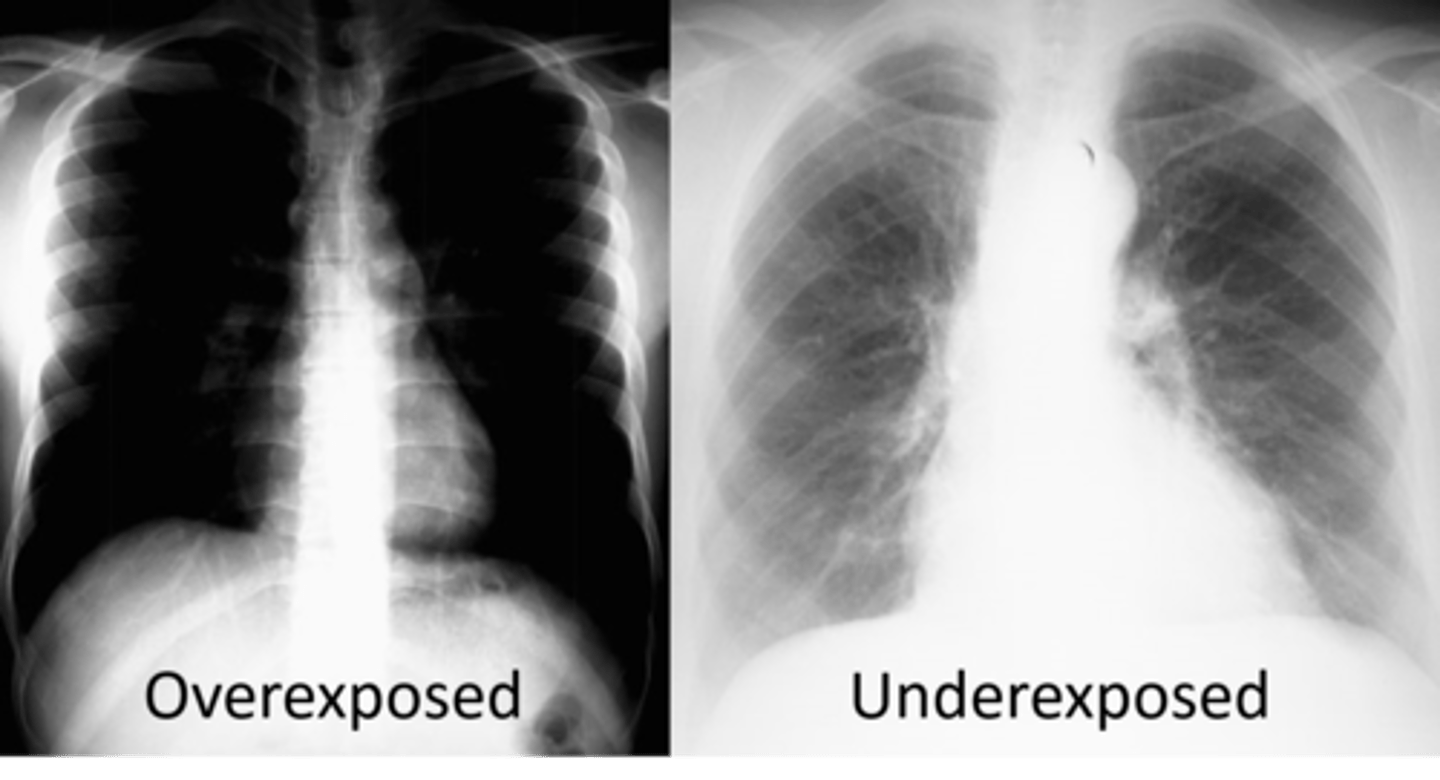

Underexposed or overexposed rads are affected by

kVp, mAs, source to plate distance

Underexposed

What is this error?

Overexposed